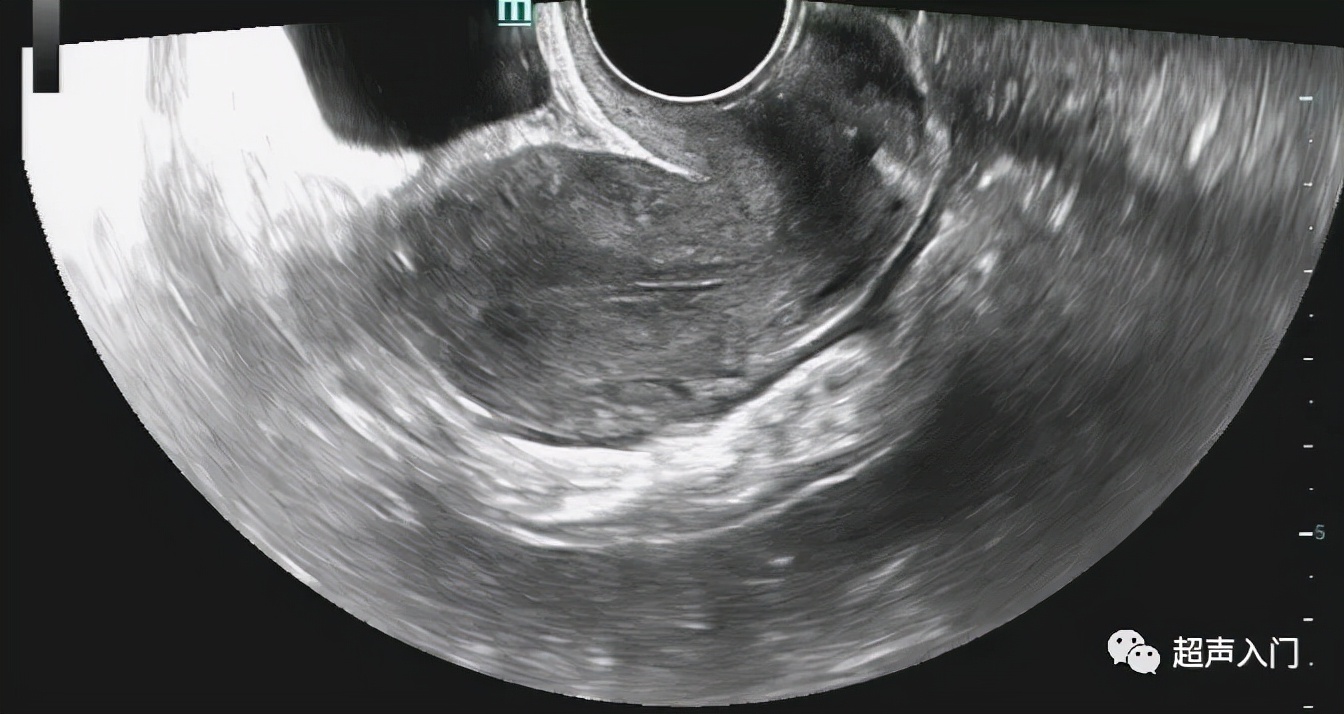

前位子宫(经阴道纵轴切面)

早孕,前位子宫(经阴道纵轴切面)